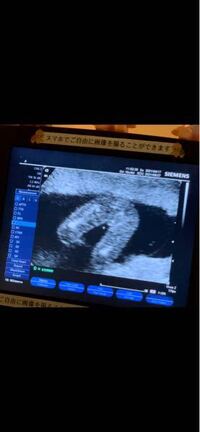

妊娠9週目 9w0d 6d のエコー写真とエピソード 妊娠3ヶ月 Cozre コズレ 子育てマガジン